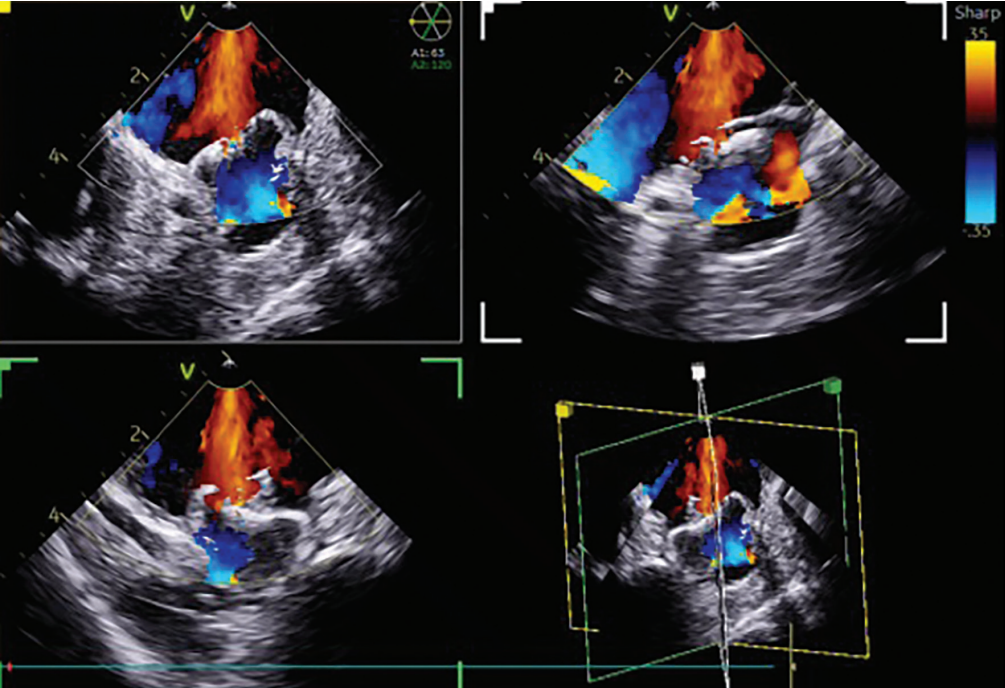

I then transitioned to the 4D ICE NUVISION Ultrasound Catheter and found that it offered superior image resolution with much less catheter manipulation due to the catheter design, as compared to 2D ICE. You can place the catheter in the left atrium in different places, and with minimal manipulation, gather the images that you need in 2D, 3D, and 4D due to its wide imaging field. The ultrasound specialist can provide multiple imaging planes at the same time, so you can quickly and coaxially visualize the device without having to manipulate the catheter. Use of ICE and NUVISION afforded more predictability, more consistent quality, and more control over the imaging, which has facilitated the implant process for me.

It is still common to use ICE for the transseptal and TEE for appendage closure. I think this adds procedural complexity, requires significant coordination, and increases patient discomfort due to the need for a TEE. The use of NUVISION for both procedures gives the electrophysiologist control over imaging quality for PFA and appendage closure. I think we have realized the importance of contact with PFA, not just with respect to lesion efficacy, but also with regard to hemolysis. When placed in the left atrium, NUVISION can be tremendously helpful due to its superior imaging quality and limited need for manipulation. We can clearly assess contact in the pulmonary veins and posterior wall and then use the same catheter for appendage closure. With a single catheter, we can visualize ablation targets and then immediately assess and guide appendage closure—all under one workflow.

I believe NUVISION NAV will be a game changer. I am most excited about CARTOSOUND integration—the ability to see the imaging plane superimposed on a 3D map will improve spatial orientation for both ablation and appendage closure. Remote UI will allow the CARTO clinical to meaningfully integrate ultrasound-guided anatomy with activation mapping. It will make ablation and appendage closure more intuitive for most operators and ensure adequate device imaging. We have data showing that 4D ICE as compared to 2D ICE is associated with fewer device redeployments. You are more likely to get the device in on the first or second try than with 2D if using 4D ICE. So, imaging quality and accuracy can really make a difference when it comes to appendage closure.

The ability to track the ablation catheter within the ultrasound field will enhance lesion visualization and contact assessment. I see this as being particularly helpful in challenging sites such as papillary muscle premature ventricular contractions (PVCs)—being able to track the catheter as you are moving along the papillary muscle in the ultrasound field will be beneficial. In general, it will facilitate ablation efficacy and real-time lesion assessment.